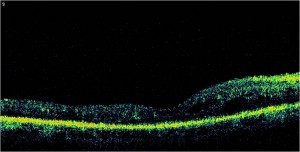

Os mostramos unas imágenes de un paciente atendido en nuestro Hospital.

Finalmente os mostramos una OCT de este mismo paciente después de ser operado donde podréis observar cómo disminuye el grosor (y por tanto el acúmulo de líquido) en la retina. Su agudeza visual experimentó una gran mejoría (de 0,2, es decir un 20%, a 0,5, es decir, un 50%)